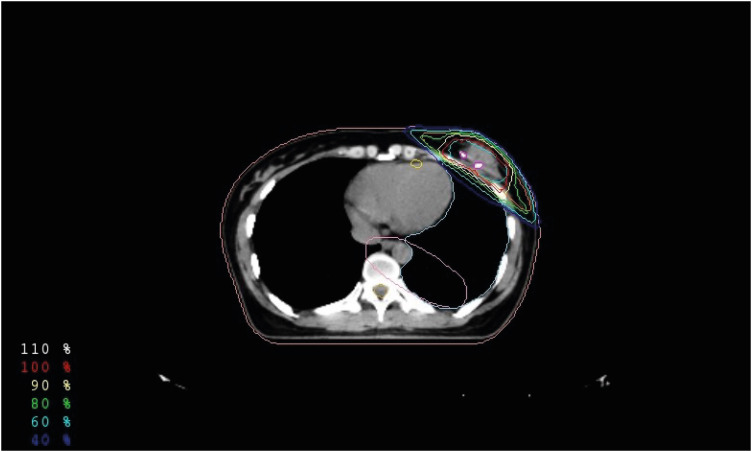

Methods: In total, 473 patients with early breast cancer or carcinoma in situ were diagnosed with Tis or T1N0 disease and underwent PBI following breast-conserving surgery. All histologic tumor types, close surgical margins within 1 mm of the tumor, and multifocal tumors were included in this study. A radiation dose of 50 Gy in 20 fractions was delivered over 4 weeks using intensity-modulated radiotherapy technique. Dosimetric data, recurrence patterns, survival outcomes, and adverse events were retrospectively analyzed.

Abstract Image